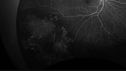

Familial Exudative Vitreoretinopathy - FEVR - Stage 4b OD384 views10 year old child with poor vision OD from birth. The left eye had vascular remodelling in the temporal periphery with preretinal abnormalitlies seen on OCT. The patient never returned for a fluorescein angiogram. Left eye is either stage 1 or stage 2. no family historyJan 01, 2019

Familial Exudative Vitreoretinopathy - FEVR - Stage 4b OD582 views10 year old child with poor vision OD from birth. The left eye had vascular remodelling in the temporal periphery with preretinal abnormalitlies seen on OCT. The patient never returned for a fluorescein angiogram. Left eye is either stage 1 or stage 2. no family historyJan 01, 2019

Familial Exudative Vitreoretinopathy - FEVR - Stage 4b OD467 views10 year old child with poor vision OD from birth. The left eye had vascular remodelling in the temporal periphery with preretinal abnormalitlies seen on OCT. The patient never returned for a fluorescein angiogram. Left eye is either stage 1 or stage 2. no family historyJan 01, 2019

Familial Exudative Vitreoretinopathy - FEVR - Stage 4b OD410 views10 year old child with poor vision OD from birth. The left eye had vascular remodelling in the temporal periphery with preretinal abnormalitlies seen on OCT. The patient never returned for a fluorescein angiogram. Left eye is either stage 1 or stage 2. no family historyJan 01, 2019